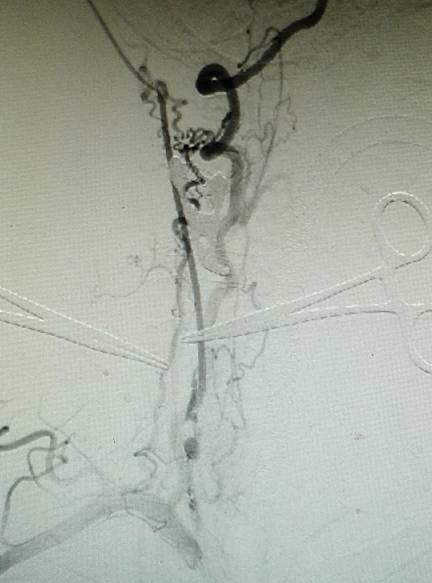

手术过程:全麻后造影示颈内动脉闭塞,经眼动脉从颅外代偿,经前交通动脉自左侧代偿。

然后行右侧颈内动脉内膜切除术,并植入动脉鞘,手术视频如下:

经动脉鞘造影,可见远端颈内动脉淡淡显影。

然后球囊扩张,植入支架。植入支架后造影示右侧颈内动脉开通。